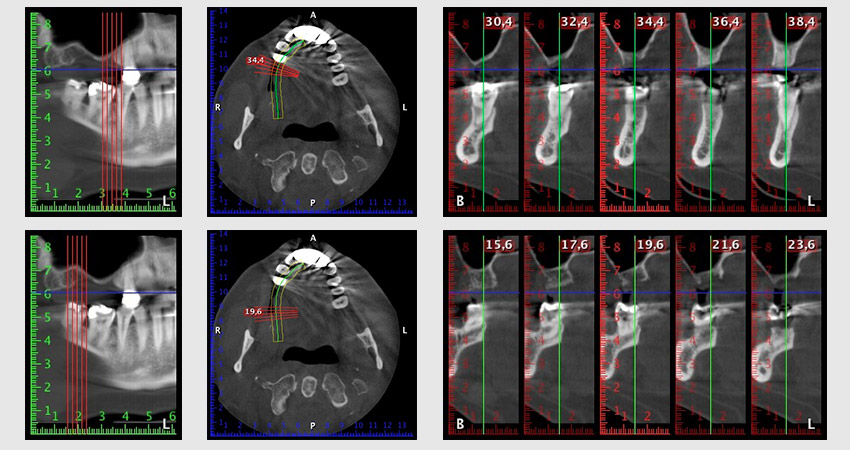

Unos seis meses después de la extracción de las piezas 16 y 14 se realizó una tomografía digital de volúmenes (DVT, Planmeca) para realizar una planificación adecuada y reducir los riesgos al mínimo. En este punto se constató que el hueso no se había regenerado en la cantidad deseada (figuras 2 a 7).

Figuras 2 a 7: Tomografía digital de volúmenes con oferta ósea horizontal reducida.

Con el fin de garantizar una restauración fija en al menos dos implantes, era preciso realizar una elevación del suelo del seno maxilar, tanto en la región 16 como en la región 14. Como en este caso la oferta de hueso residual era extremadamente reducida, fue preciso realizar una retirada ósea relativamente grande. Los procedimientos de retirada ósea grande son invasivos y, además, están asociados a una mayor morbilidad del paciente, llevan más tiempo y resultan más costosos. También es más difícil prever los resultados del tratamiento y el riesgo de fracaso es mayor. Teniendo como telón de fondo estas desventajas, la paciente recibió información sobre la posibilidad de utilizar una alternativa extraíble, pero ella la rechazó firmemente.

Para limitar el aumento a la región 14, se mantuvieron conversaciones con la paciente y se acordó una incorporación oblicua del implante 16 hacia la zona dorso-craneal (figura 8).

Imagen 8: Tomografía digital de volúmenes del ángulo de inserción para el implante 16.